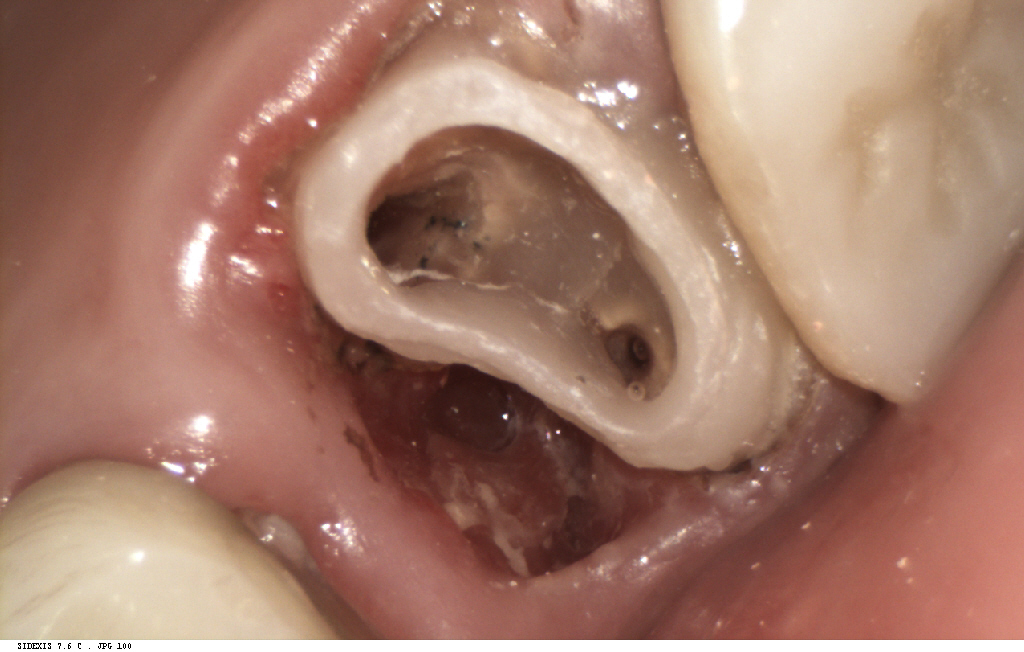

まず初診時に詳細な検査を行い、

その後マイクロスコープとラバーダム

(薄いゴムを用いて無菌状態で今回治療を行うための処置)

を使用した精密根管治療で

感染源を徹底的に除去しました。

続いてファイバーコア

(歯根の強度をあげるために土台としてしん棒をいれる処置)

による補強を行い、

歯の土台を整えたうえで、

最終的にセラミッククラウンを装着しました。